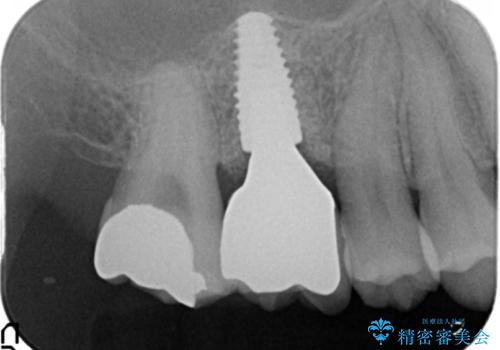

骨量が不十分であった為、ソケットリフトを併用しインプラントによる補綴計画を立てます。

- 50万円(ストローマンインプラント・ソケットリフト・ジルコニアカスタムアバットメント・ジルコニアクラウン)費用は治療当時の料金となります

ソケットリフトについて

上顎のインプラントは、上顎洞底までの距離が短い場合ソケットリフト法を行い骨量を増やしたのちにインプラント埋入を行うことでより長期的な予後を見込むことができます。